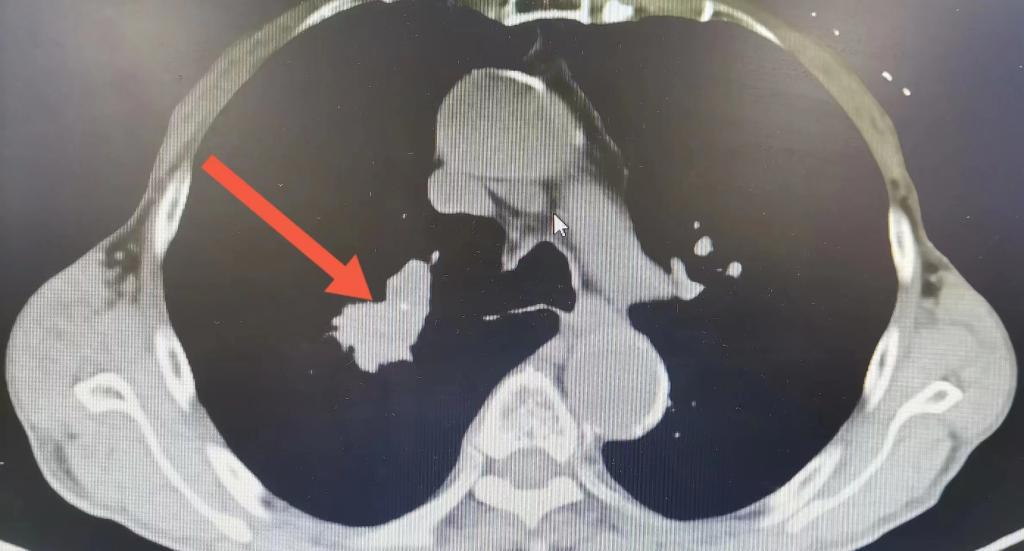

患者是一名80岁的高龄男性,因“痰中带血1月余”入我院胸外科。患者完善增强CT:右肺上叶考虑占位;双肺考虑慢支气肺气肿改变;行支气管镜检查提示:右肺上叶开口新生物,组织病理检查提示为:肺鳞癌,并完善其他相关检查,排除手术禁忌症后,与患者及家属充分沟通后同意行手术治疗。